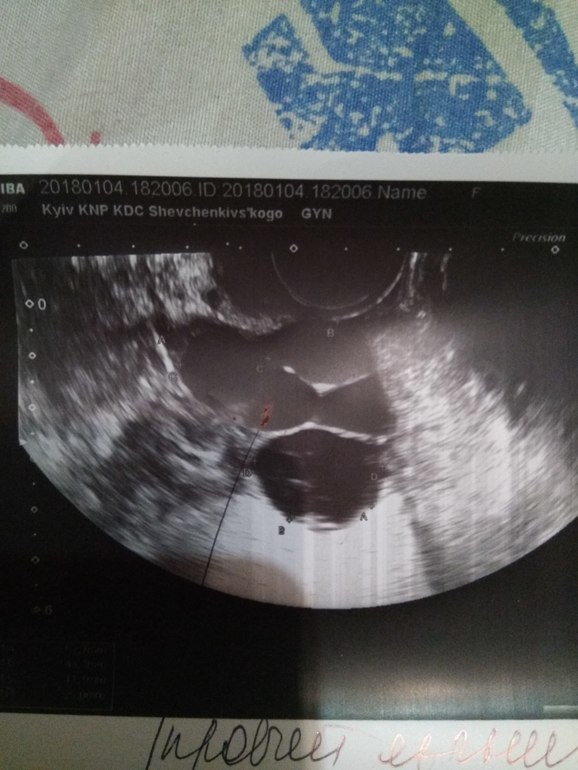

Вот даже фоточку покажу)

Гормоны у меня все зданы и первой фазы и второй, это самое первое что сделали + 3 узи, ну последнее я описала. Из гормонов проблема была только в прогестероне 0,59 на 22дц и дега-с 424 . Тестостерон, пролактин, ФСГ,лг,17 он в норме. Как-то так вот. Что делать не пойму. Ну и не пойму откуда картина гиперстимулированного яичника)))

Опять бхб? 46 дц, мфя